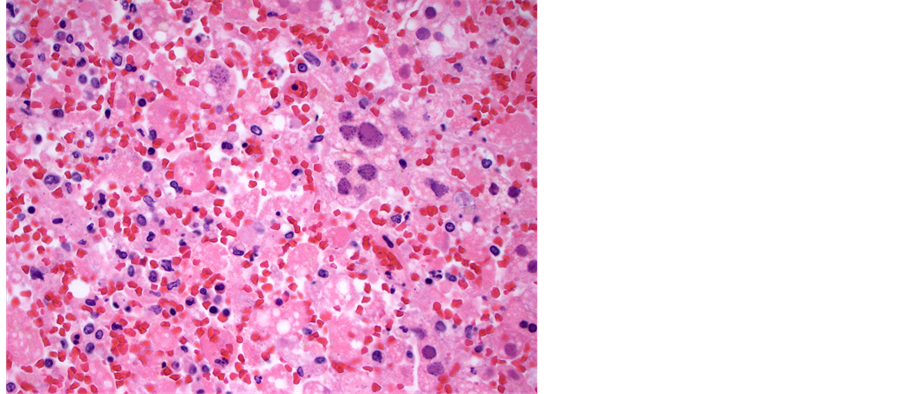

examined showed any signs of viral infection, inflammation or necrosis, including the central nervous system, gastrointestinal tract, larynx and trachea. Viral inclusions were presents and presence of HSV was confirmed with immunohistochemical stain. The liver was slightly enlarged (2128 grams, reference range, 1500 - 1800 grams), and had firm, dark red parenchyma. Microscopically, the liver parenchyma was diffusely necrotic (Fig- ure 1), with minimal cellular detail, and with abundant parenchymal hemorrhage. Many of the viable hepatocytes had enlarged, deeply basophilic nuclei with the characteristic “ground glass” chromatin pattern that in some instances resemble ground glass nuclear inclusions (Figure 2). Other nuclei had the characteristic punctate, granular chromatin pattern (Figure 3). Although the histologic features are quite characteristic of herpes virus infection, this was confirmed with an HSV immunohistochemical stain (Figure 4). These nuclear changes are commonly refered to as “viral cytopathic effect,” and were observed in essentially all sections of the liver examined.

Figure 2. Medium power view of liver parenchyma demonstrating the inclusion-like ground glass change in an enlarged hepatic nucleus. The surrounding parenchyma is completely necrotic (hematoxylin and eosin, 200× magnification).